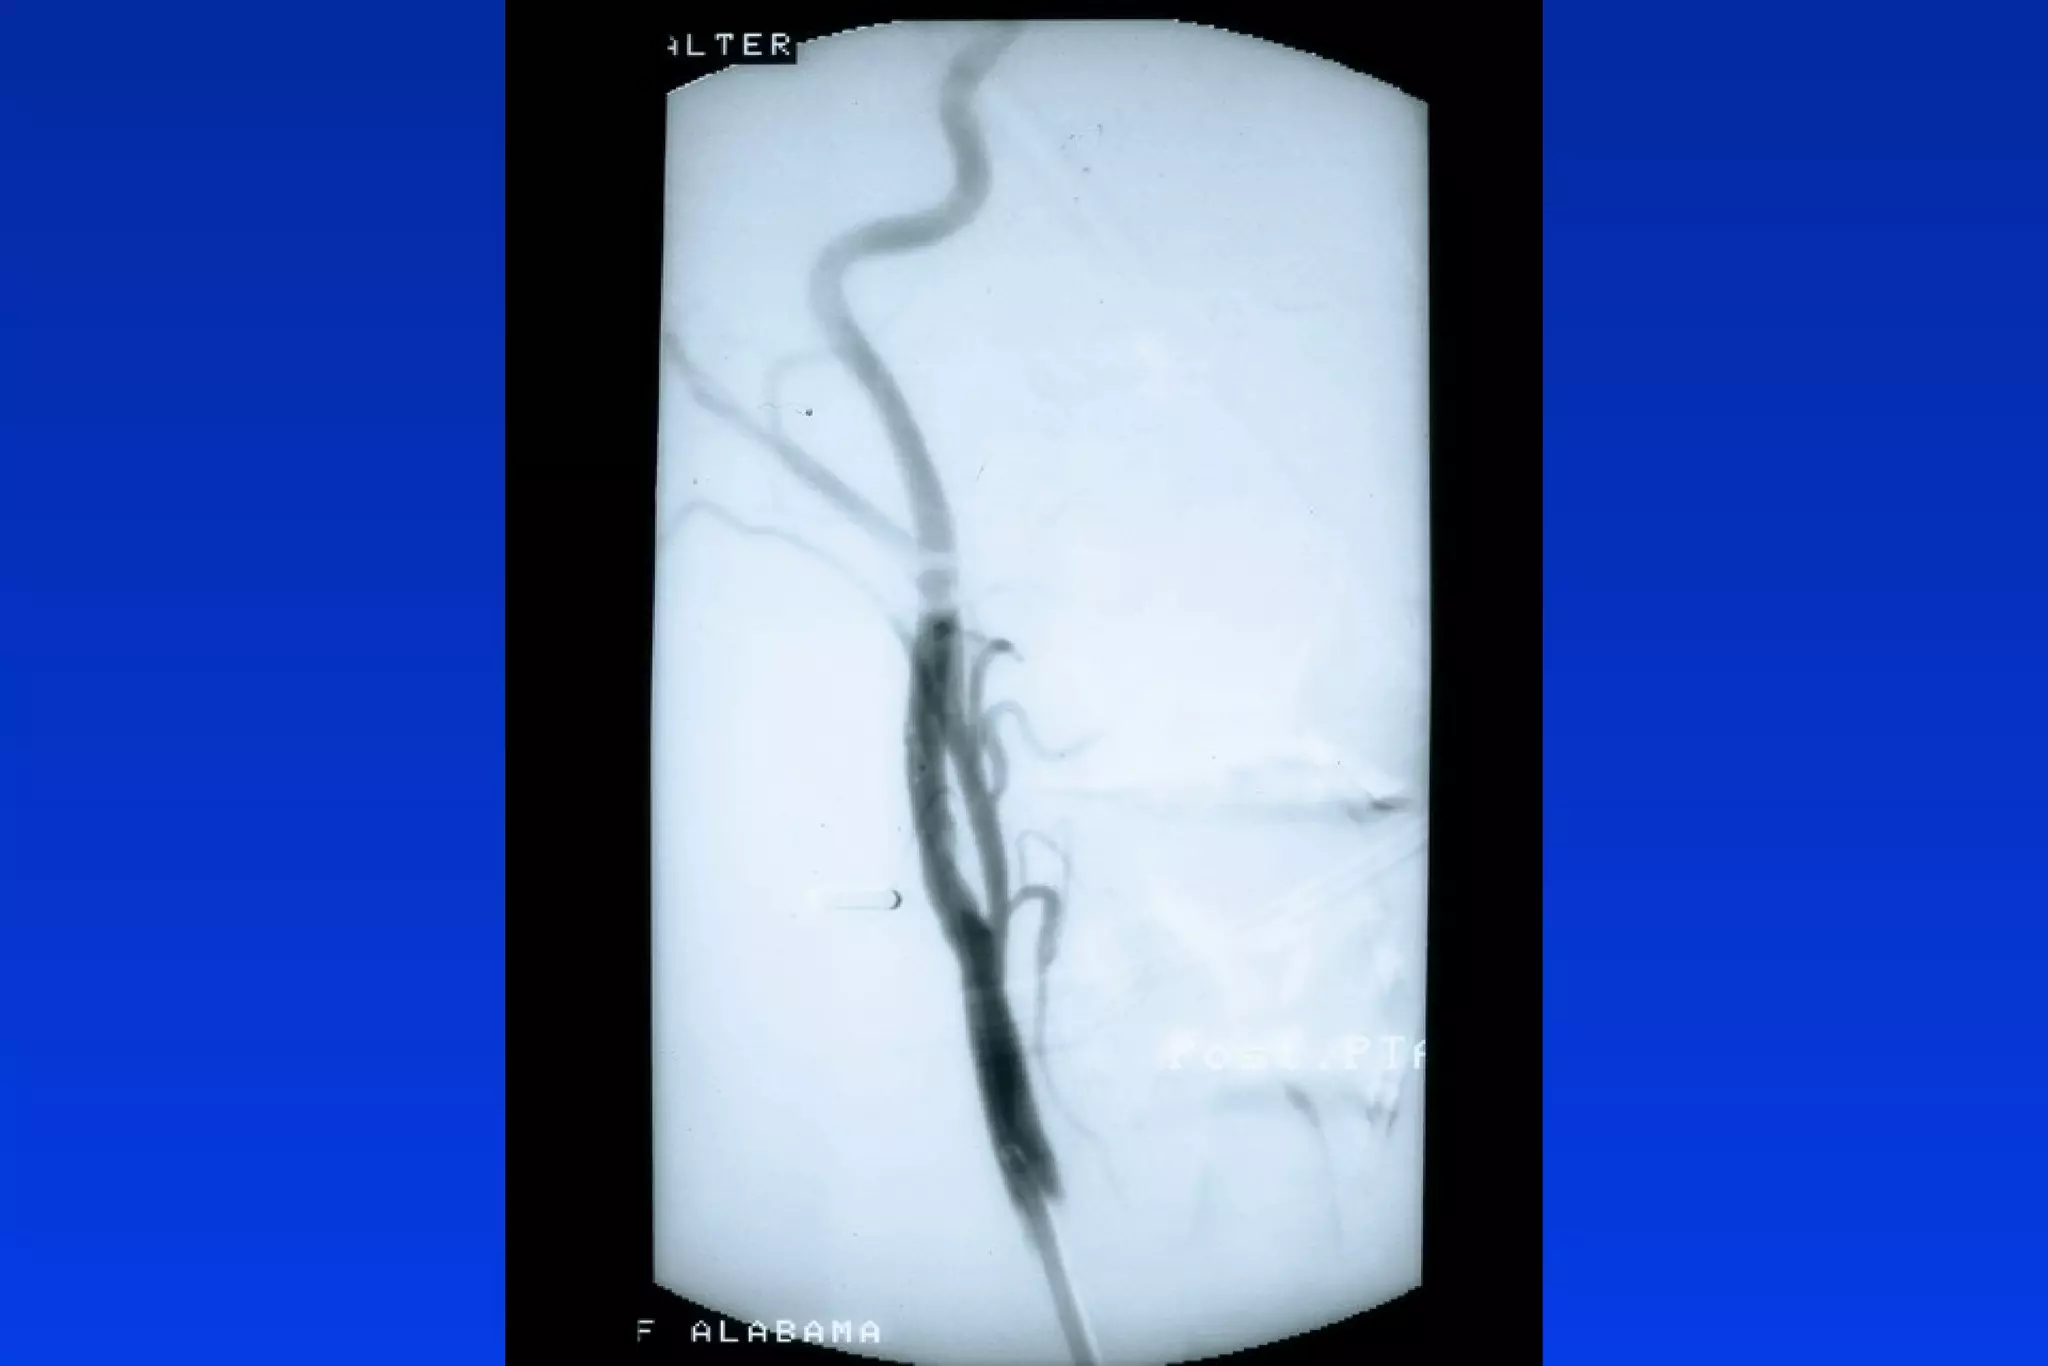

Occlusive:

– Distal Flow Arrest

» Theron - Balloon Occlusion Catheter

» PercuSurge - Balloon Occlusion Guidewire

– Proximal Flow Arrest

» Arteria- Balloon Occlusion Guide

Catheter